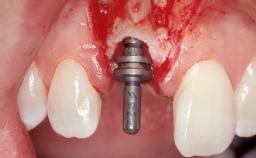

A 30-year-old female patient had lost tooth 21 and was referred to our clinic for consultation and treatment. Due to advanced apical infection, tooth 21 had been extracted two months earlier at another clinic and an acrylic-resin tooth had been bonded to the adjacent teeth. The patient desired implant treatment to avoid any damage to the adjacent natural teeth. While the patient had no history of any systemic disorder, she was a heavy smoker and exhibited medium to advanced periodontitis in the entire jaw. After the initial treatment to achieve a pocket probing depth of less than 4 mm and no bleeding on probing, a decrease in the height of the papillae mesial and distal to the extraction site and overall gingival recession were observed.

Type of Implants One-Piece|Reduced-Diameter

Placement Protocol Early or late implant placement

Bone Volume Deficient horizontally, requiring prior grafting